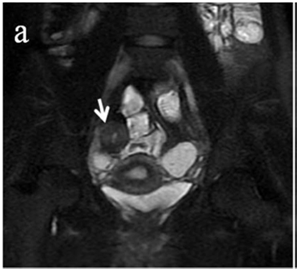

Figure 4 (a) Coronal SSFSE (singleshot fast spin echo) T2-weighted image with fat suppression (b) axial FIESTA (fast imaging employing steady-state acquisition) image show wall thickening (white arrow) and stenosis of the lumen in the terminal ileum. Note the prestenotic dilatation in b (white arrowhead). (c) Neoterminal ileum wall is thickened and has high signal on diffusion-weighted (DW) image (b= 800 s/mm2) (white arrow) and dark signal (black arrow) on the apparent diffusion coefficient (ADC) map in (d) indicating restricted diffusion. (e,f) ADC value measurement from the wall of the terminal ileum on magnified DW image. (e) and corresponding ADC map (f): ADC value = 1.20 × 10-3 mm2/s

Figure 5 Comparison of coronal (a) and axial (c) DWI sequences with the respective

after contrast medium injection (b, d).